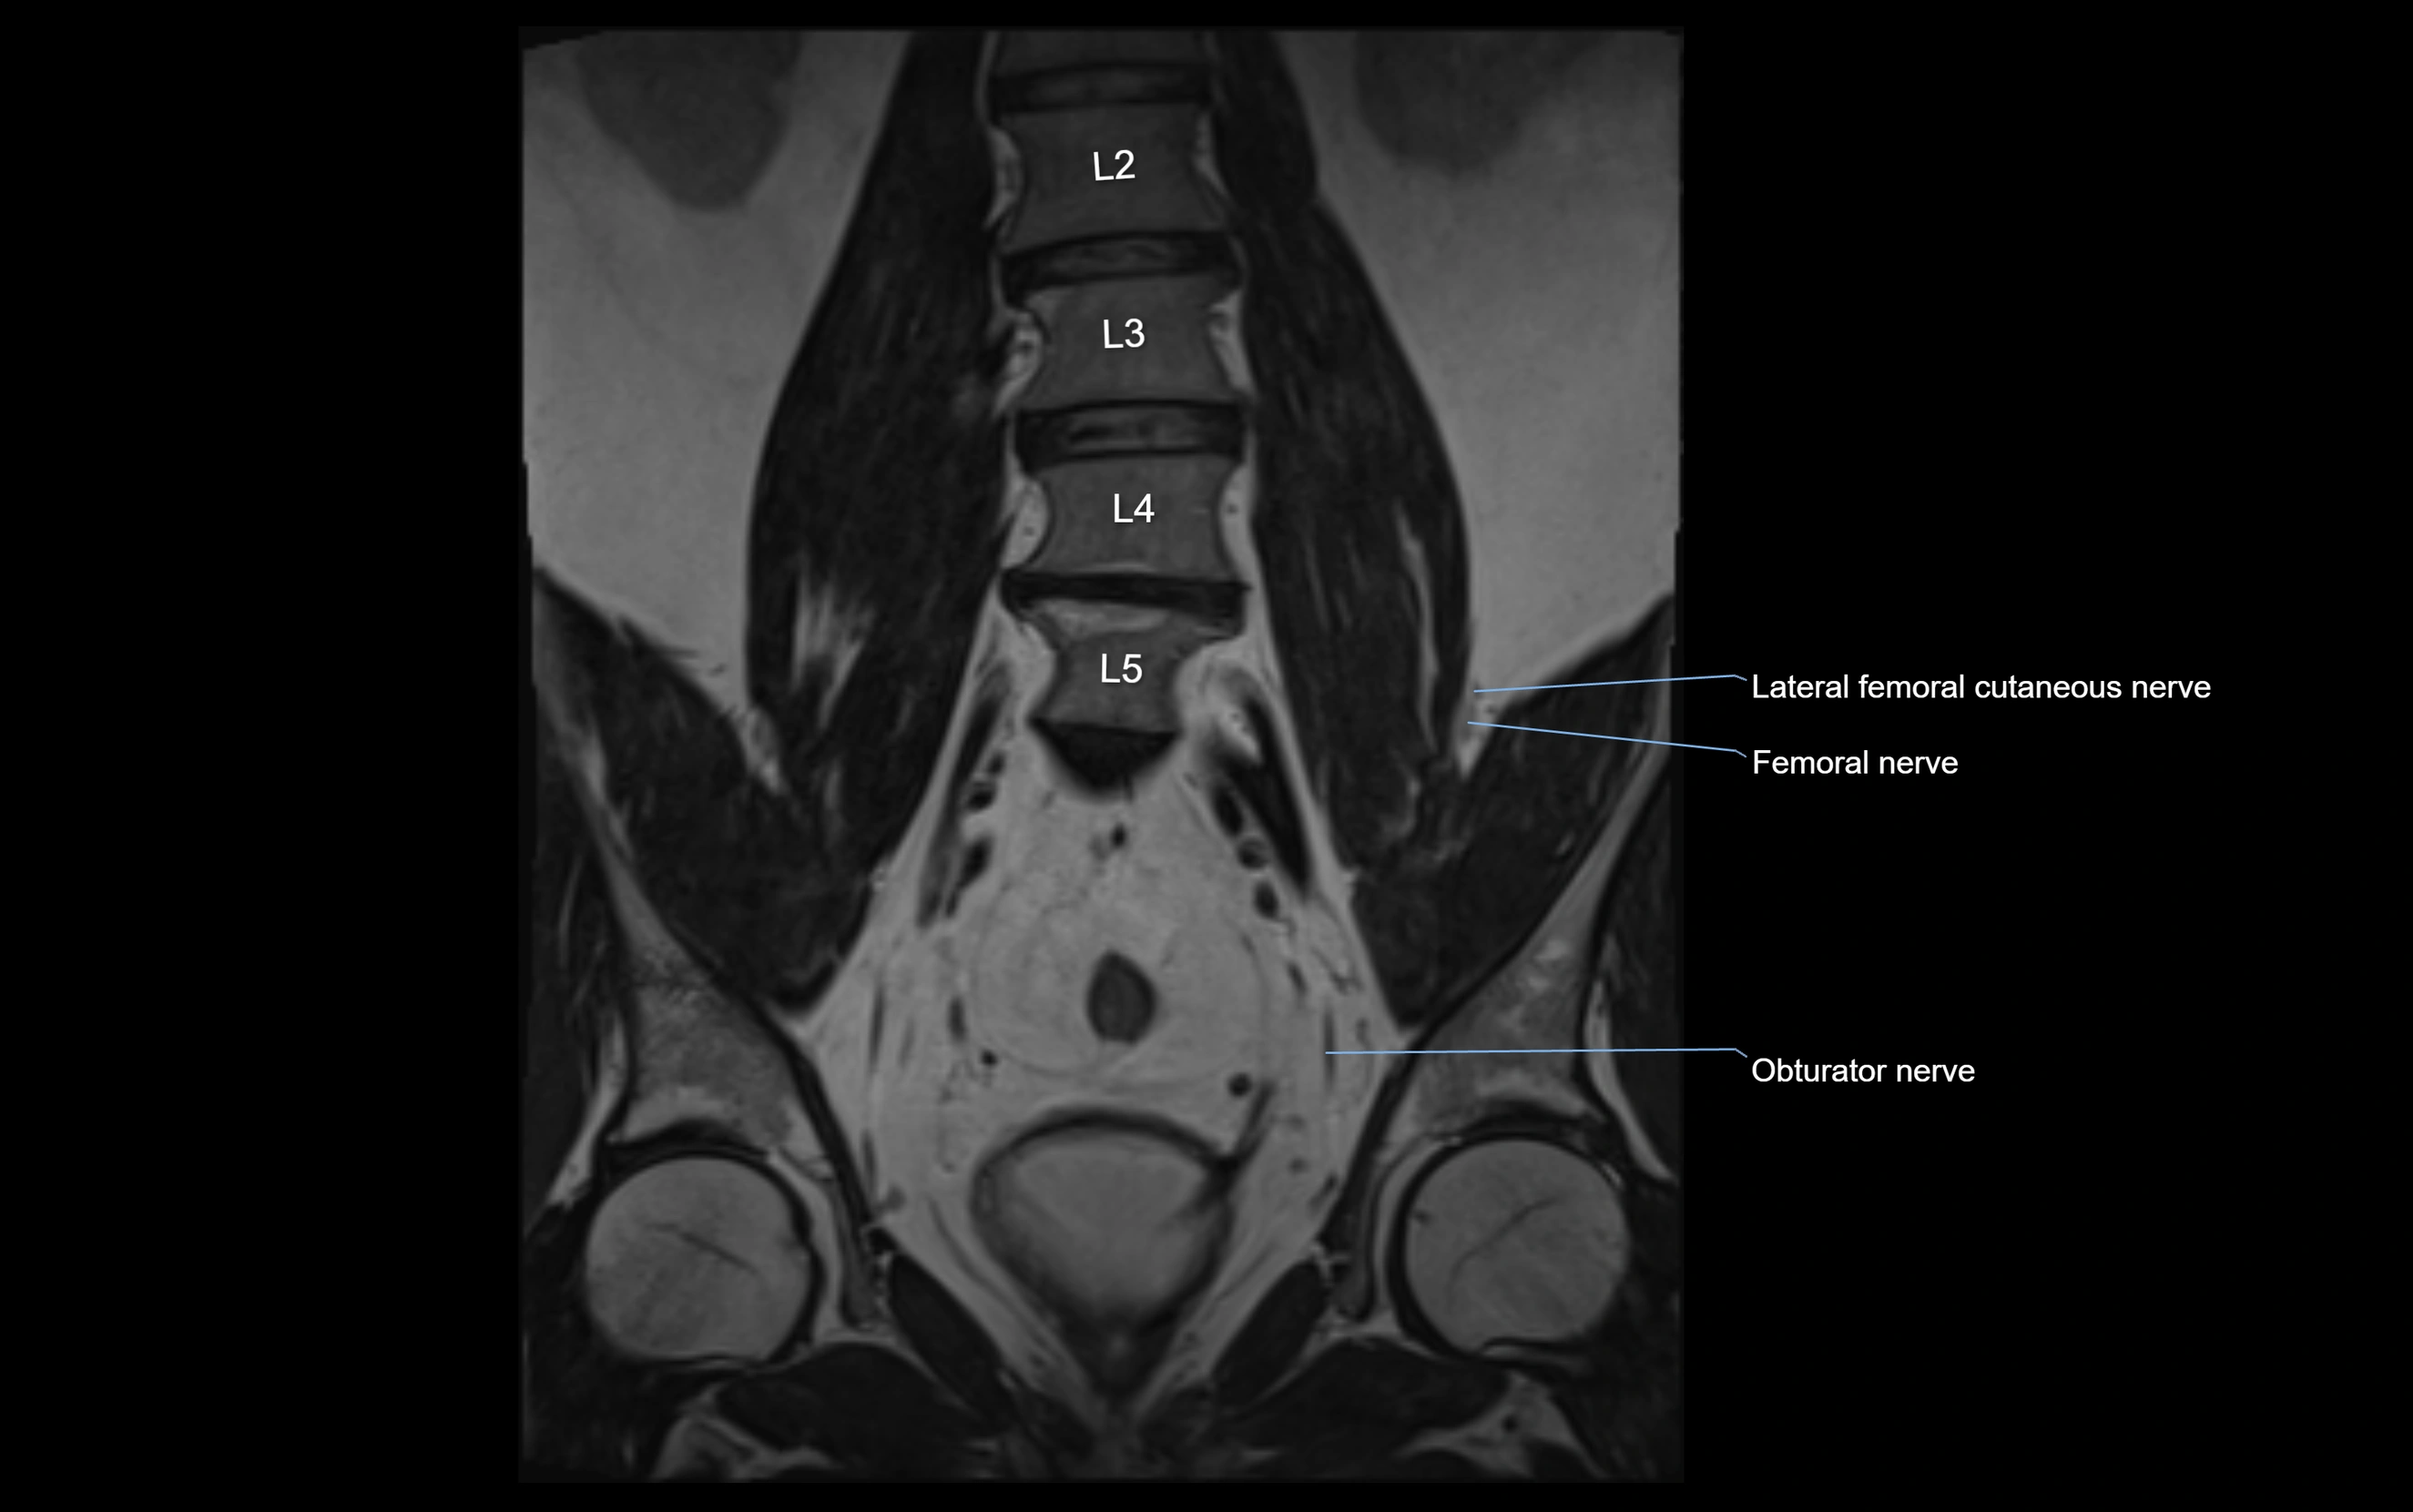

MRI Appearance

T1-weighted images:

• Nerve appears as a very thin low-to-intermediate signal intensity structure

• Surrounded by bright fat, aiding visualization

T2-weighted images:

• Nerve shows intermediate to mildly hyperintense signal compared to muscle

• Pathological involvement appears brighter

STIR (Short Tau Inversion Recovery):

• Normal nerve appears dark

• Inflamed or entrapped nerve appears bright hyperintense

T1 Fat-Sat Post-Contrast:

• Normal nerve enhances minimally

• Pathologic nerve (neuritis, entrapment, tumor infiltration) shows focal or diffuse enhancement

3D T2 SPACE / CISS:

• Nerve appears intermediate to mildly hyperintense compared to muscle

• Surrounded by bright fat or CSF, improving visualization

• Best sequence for mapping small pelvic nerves such as the anococcygeal